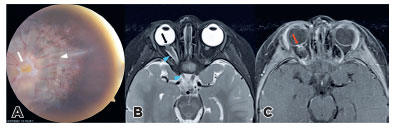

A 2-year-old patient had right ocular esotropia for 1.5 years. Right fundoscopyrevealed a large disc, central glial tuft (arrow), and a halo of pigmentary changes in the peripapillary area surrounding the nerve (arrowhead) consistent with methylglycinediacetic acid (MGDA) (Figure 1A). Funnel-shaped morphology of the optic disc (black arrow), adjacent retinal surface elevation and enhancement (red arrow), and irregular thickening of the nerve (blue arrowheads) were detected (Figure 1B, Figure 1C). Irregular thickness of optic nerve occurs in 89% MGDA, the nature being uncertain(1-3).